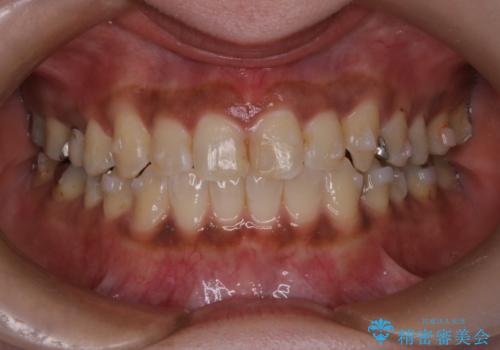

【インビザライン】前歯の凸凹をなおしたい

- 前歯の凸凹を主訴に来院されました。

インビザライン にて治療を行い、歯並びの改善を行うことができました。